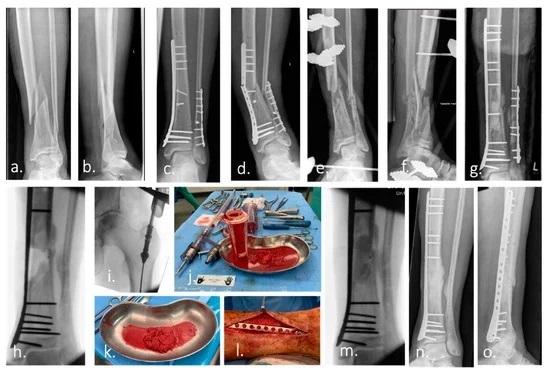

ترمیم استخوان با برق

۲۹ اکتبر ۱۹۷۱ میلادی برابر با ۸ آبان ۱۳۵۰ خورشیدی، اولین استفاده موفقیتآمیز از جریان الکتریستیه برای ترمیم شکستگی استخوان ازسوی جراحان دانشگاه پنسیلوانیا گزارش شد. رابطه بین نیروهای فیزیکی و زیستشناسی استخوان از اواسط سده نوزدهم شناخته شده است. نیروهای مکانیکی، نیروهای الکتریکی، نیروهای مغناطیسی و امواج فراصوت همگی در سطوحی از تأثیر بر رشد و ترمیم استخوان تاثیر دارند. تحریک الکتریکی استخوان بهعنوان یک روش موثر و غیرتهاجمی برای افزایش ترمیم استخوان و درمان جوش نخوردن شکستگی معرفی شده است. وقتی استخوان انسان خم یا شکسته میشود، بار الکتریکی ایجاد میکند. این بار الکتریکی کم، سازوکار ترمیم داخلی بدن را تحریک میکند. متاسفانه، شواهد بالینی برای اثربخشی تحریک الکتریکی محدود است اما نمونه معرفیشده از سوی جراحان دانشگاه پنسیلوانیا از نمونههای موفق در این حوزه بهشمار میرود.